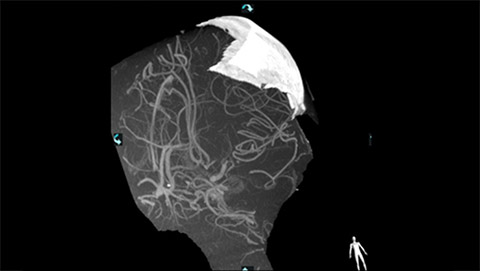

VasoCT visualizes small intra-cranial devices in vessel context with unmatched spatial resolution. Metal Artifact Reduction decreases streaking artifacts as from coil mass close to intra-cranial devices.

VasoCT (Allura X-ray system with dedicated EPX settings + XperCT + intravenous contrast injection) provides high-resolution imaging of intracranial arteries to help visualize location, size, and direction of an occlusion in case of Ischemic Stroke.